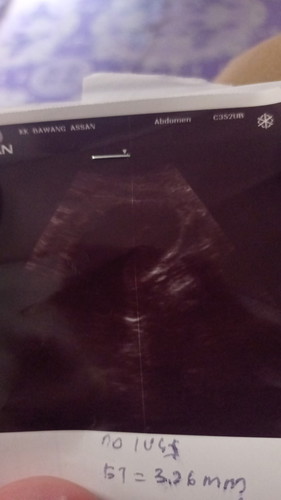

Saya nak mommy sapa ada macam saya scan 7minggu nampak kantung saja dr suruh repeat scan 2week lagi.

rasa sedih dr scan nampak kantung je

saya.. 7 weeks nampak kantung ja. doc suruh repeat scan 2 minggu. baru nampak baby 💕💕